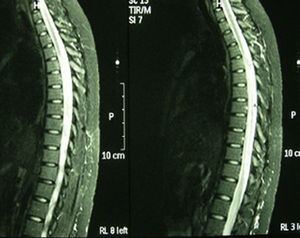

Case 3: 22-year-old Caucasian female, diagnosed with SLE at age 15 on the basis of polyarthritis, cutaneous and mucosal involvement, lymphopenia, positive ANA and anti-DNA at high titers. A renal biopsy due to persistent urinary abnormalities showed type IV lupus nephritis, and therapy with cyclophosphamide, prednisone and hydroxychloroquine was started. She came to the clinic with lumbar pain, dysuria, and asthenia, with gradual introduction of paresthesias in the right abdomen and lower limb paresis. Laboratory tests showed a WBC count of 30,000×910 (no left shift), erythrocyte sedimentation58mm/h, C-reactive protein6.41mg/dl and lactic acid 1.10mmol/l. Repeated analysis of blood and urine cultures were negative. Serology showed positive ANA 1/320, anti-DNA of 167U/ml, negative antibody antiphospholipid antibodies. MRI of the spine (Fig. 2) reported a large segment of myelophaty in the dorsal spinal cord. Cranial MRI changes observed in the left cerebellar hemisphere were a signal that could be related to lupus vasculitis, showing diffuse hyperintense signal in FLAIR and T2. No gadolinium was used upon patient request. After a lumbar puncture, a normotensive transparent liquid was obtained with 58mm3, 80% polymorphonuclear cells, 20% lymphocytes, glucose 127mg/dl, Protein1015mg/dl and lactate dehydrogenase 216U/l. Gram staining of cerebrospinal fluid showed no bacteria and fungal culture and CO2 were negative. She was treated with bolus methylprednisolone and 48h later she presented seizures which were resistant to treatment with valproic acid. She was interned in the intensive care unit, where treatment was initiated with phenytoin and midazolam for seizure control as well as tuberculosis treatment, cephalosporin and prophylactic acyclovir. After a feverish peak she showed an abrupt neurological deterioration, with Glasgow 8/15. Cranial computed tomography showed a massive and generalized cerebral edema with effacement of sulci and cisterns, not differentiating between white and gray matter. Contrast administration showed that intracranial circulation barely existed, with widespread signs of ischemia. Bradycardia and complex aberration triggered cardiorespiratory arrest.

Regarding diagnosis, MRI is the determining test. Studies show abnormality of signal with hyperintensity on T2, gadolinium enhancement and edema of the spinal cord. No specific images exist by etiology, although multiple small lesions seem indicative of SLE, while very extensive lesions and abnormalities at various levels are more indicative of vasculitis.12 On brain MRI in T2/FLAIR demyelinating lesions, with marked involvement can be found, as in our case 1. The study of cerebrospinal fluid may show inflammation of the spinal cord, with pleocytosis or elevated IgG values. In the basic immunological study we find antimyelin antibodies (which can predict the evolution of a clinically isolated syndrome to multiple sclerosis) and antiaquaporin 4 antibodies. Recurrence of TM has been associated with the presence of anti-Ro/SSA antibodies.13 However, it is precisely our case of SS with repeat episodes (case 2) which does not have anti-Ro/SSA or anti-La/SSB antibodies, basing the diagnosis on clinical and histological criteria.